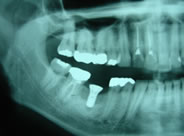

下顎の奥歯が1本ありません

レントゲンで欠損とその周囲の状態を調べます

埋入するインプラントを決定します

手術時間は30分程度でした

インプラントのX線像

セラミックの歯が入り良く噛めるようになりました